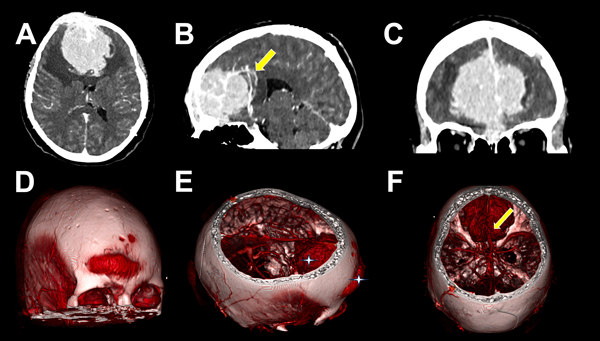

Figura 1. A, B, C) TC contrastada y angioTC preoperatoria. A) Lesión extraaxial, circunscripta, en topografía del surco olfatorio, con realce homogéneo a la administración de contraste y edema vasogénico perilesional. B) Desplazamiento de arterias pericallosas y rodilla del cuerpo calloso hacia posterior (flecha amarilla). C) En corte coronal se evidencia base de implantación frontobasal y desplazamiento de polos frontales hacia lateral. D, E, F) TC con reconstrucción 3D. D) Componente exofítico transcraneano bifrontal. E) Compromiso extra e intracraneal de lesión (cruces blancas). F) Lesión voluminosa e hipervascularizada, se evidencian arterias pericallosas desplazadas hacia posterior (flecha amarilla).

En el estudio de resonancia magnética (RM) de encéfalo se observó lesión extraaxial expansiva bifrontal con compromiso del seno frontal y tercio anterior de seno sagital superior de aspecto sólido e hipervascularizada, de aproximadamente 5.2 x 5.8 x 7.7 cm. Lesión isointensa en secuencia T1 e hipo-hiper intensa en secuencia T2, que realzaba de manera homogénea a la administración de contraste paramagnético con engrosamiento leptomeníngeo asociado. En secuencia FLAIR, se evidenció edema perilesional con colapso de las astas ventriculares frontales. En AngioRM se advirtió un gran aporte vascular de ambas arterias cerebrales anteriores, y en ventana ósea, múltiples lesiones osteolíticas en calota craneana (Figura 2).

Se han descripto dos patrones de extensión, la diseminación hematógena de células plasmáticas y la diseminación continua directa desde lesiones líticas erosionadas del cráneo.1,12 En cuanto al diagnóstico diferencial, destacan las similitudes imagenológicas con los meningiomas, tumores que surgen de las células aracnoideas de la duramadre y constituyen una de las neoplasias intracraneales más comunes. En RM suelen verse como una masa extraaxial redondeada de bordes suaves y circunscrita con base ancha en la superficie dural, presentan hipointensidad en secuencia T1 e hiperintensidad en secuencia T2 con realce homogéneo a la administración de contraste y el signo de “cola dural” que no es patognomónico de esta entidad y puede advertirse en otras lesiones como hemangiopericitoma, metástasis o linfomas; esto hace casi indistinguible la diferenciación preoperatoria en casos como este (ver Figuras 1 y 2).